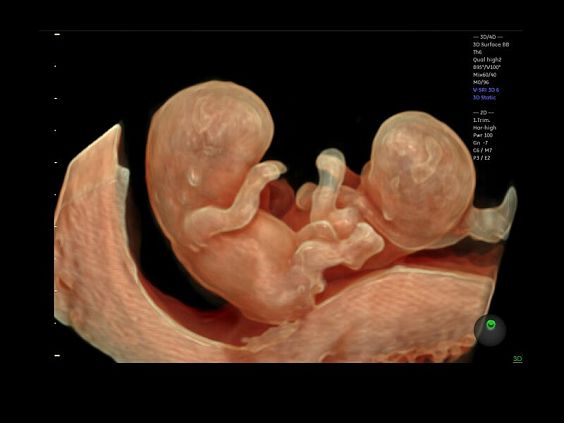

• Программа объемной визуализации плода классический HD-Live + расширенный пакет Hdlive Silhouette и Studio:

• HDlive Flow - перемещаемый источник света, совместимый с визуализацией кровотока в 3D

• HDlive Silhouette - режим "Силуэт" с подчеркиванием границ тканей и объектов, "объем в объеме"

• HDlive Flow Silhouette - режим "Силуэт" с выделением границ полостей сердца и сосудов, совместимый с визуализацией кровотока

• HDlive Studio - три независимых источника освещения с регулировкой интенсивности

• Автоматическое определение плода в режиме 3D (SonoRenderLive) – позволяет значительно экономить время и получать изображение конечностей и лица плода в режимах 3D без артефактов и помех – система автоматически определяет границы конечностей и лица плода и выстраивает объемное изображение

Объемное сканирование Voluson — 3D/4D вашей мечты

Объемное УЗИ на Voluson E10 — это не просто потрясающе красивая картинка, это ценный инструмент получения дополнительной информации при обследовании женщин.

Voluson E10 поддерживает инновационные технологии формирования изображений — HDlive Silhouette и HDlive Flow, которые позволяют увидеть мельчайшие детали. Алгоритм SonoRenderlive упрощает рабочий процесс и дает возможность реконструировать изображение поверхностей, определяя область перехода между тканью и жидкостью.

• HDlive

Инновационная технология визуализации HDlive обеспечивает получение реалистических изображений за счет эффекта объемного зрения, повышая достоверность клинической оценки. Теперь режим HDlive дополняют две новые функции:

• Технология HDlive Silhouette — задает разный уровень прозрачности, помогая выявлять контуры внутренних структур и точнее оценивать состояние плода в первом триместре.